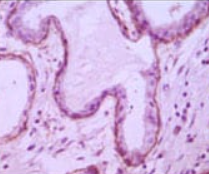

IHC    1/200 - 1/1000